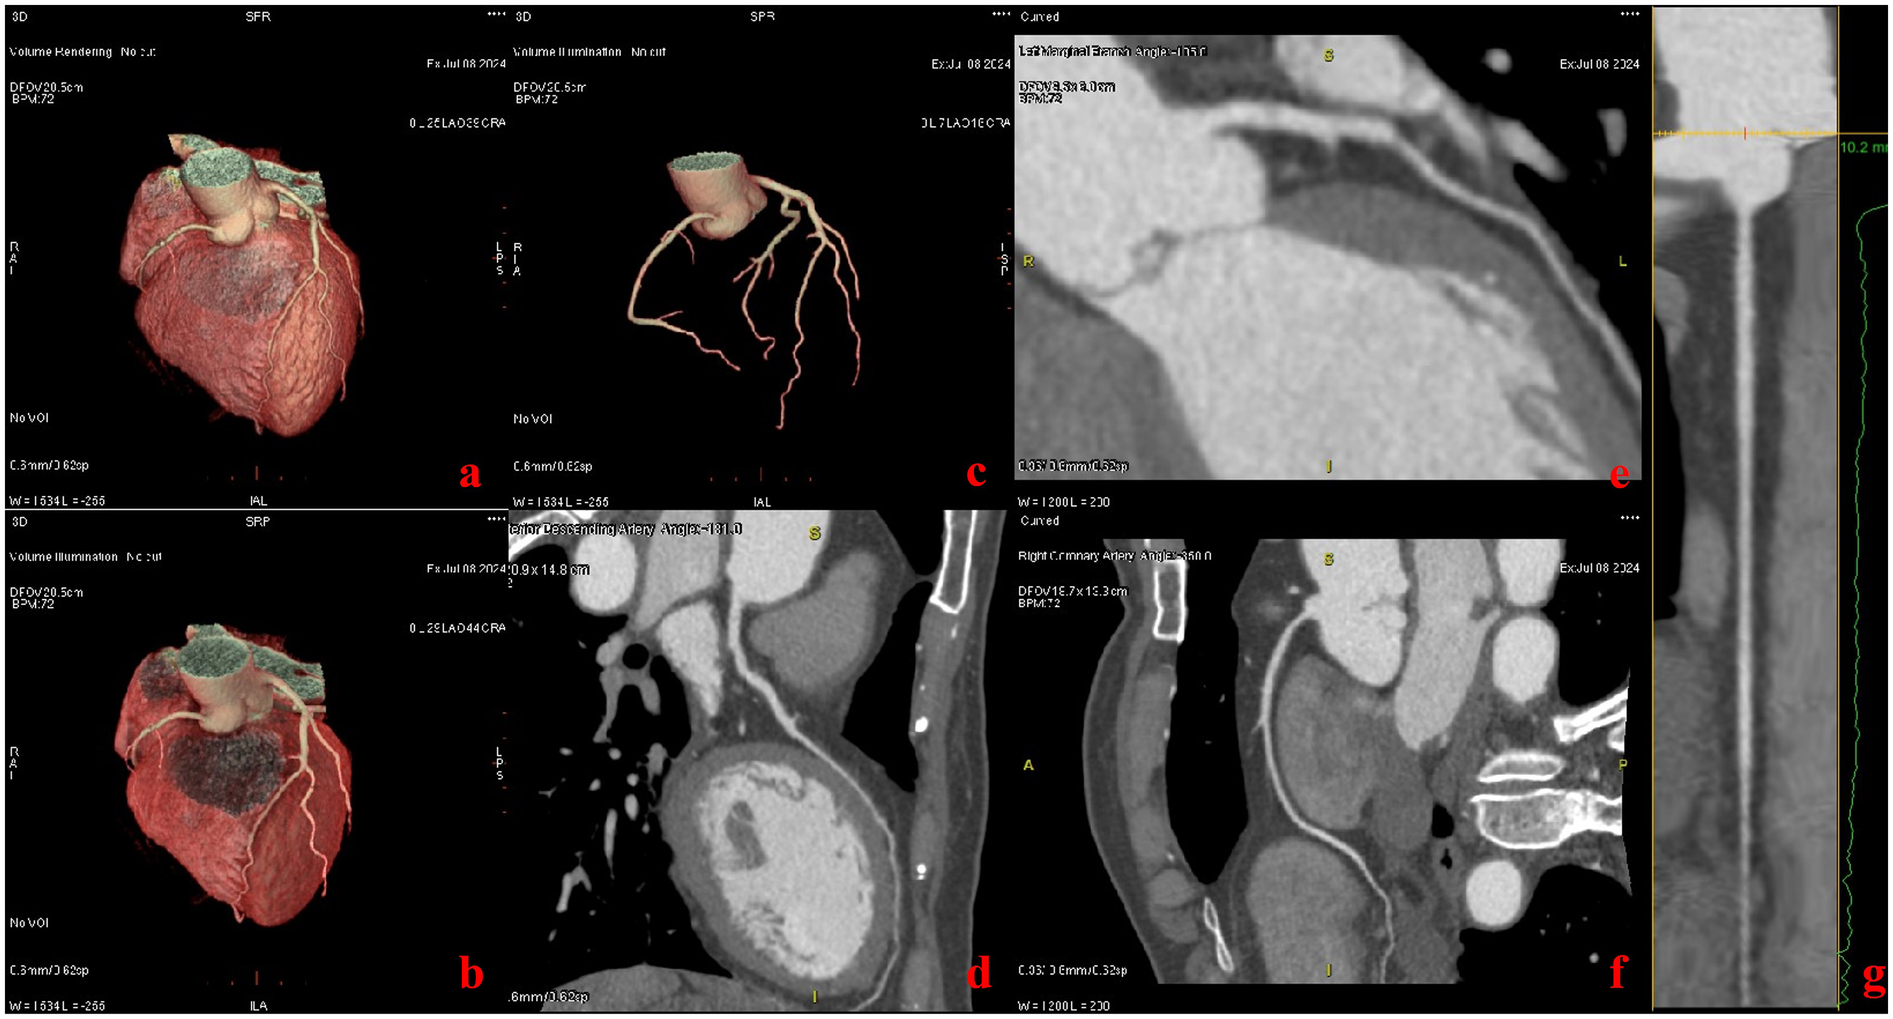

Figure 2

Patient with chief complaint of chest pain (heart rate: 68 bpm). Images were acquired with the ECG-less CCTA. Volume rendering reformat CT images show the heart (a–c). Curved multiplanar reformat CT images show the left anterior descending artery (d), left marginal branch (e), and the right coronary artery (f, g).